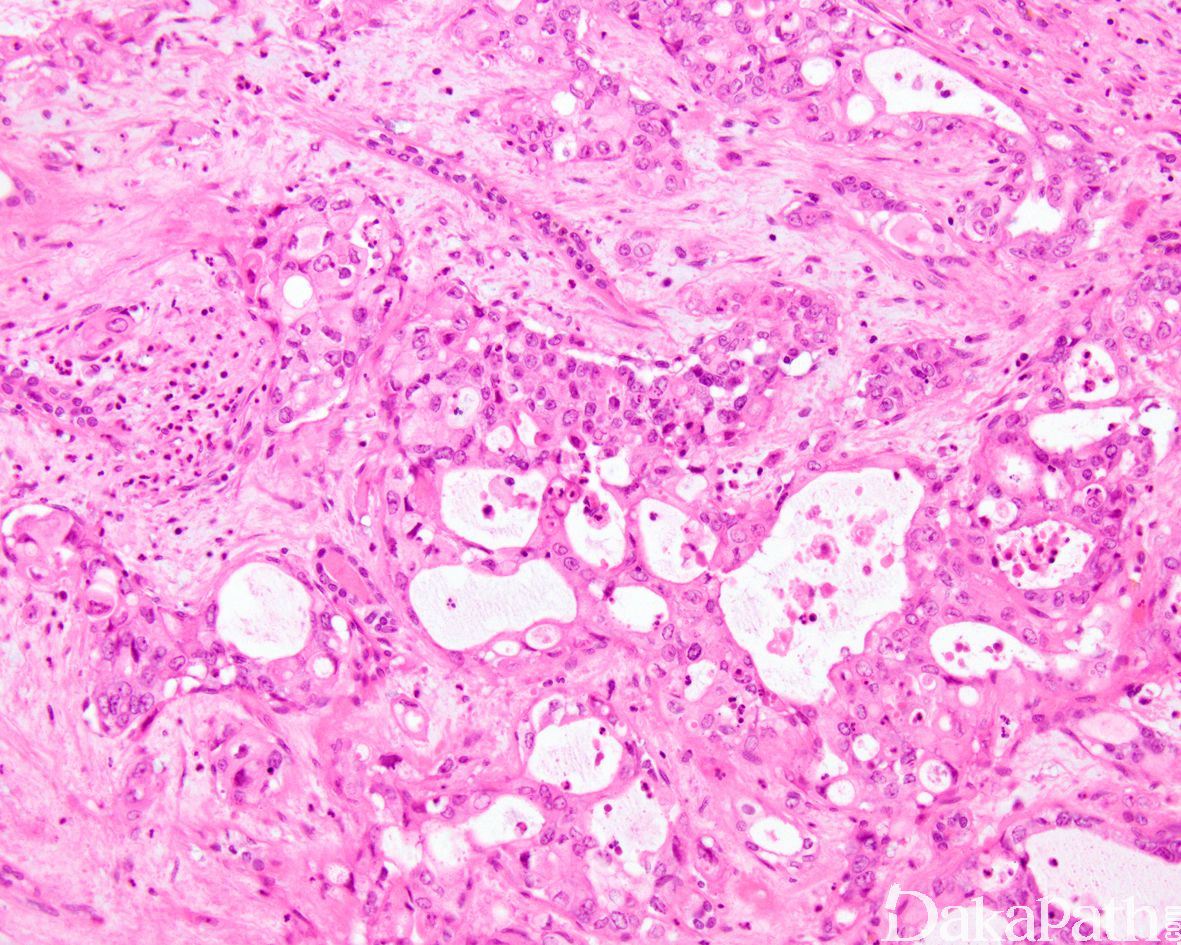

Renal Cell Carcinoma,Unclassified

并非独立的肿瘤类型,当肾细胞癌类型不属于特指的各个类型时,将之归为未分类的肾细胞癌。

形态学不属于特指的各个类型。

组织学特征不能归类为特定的肾细胞癌类型,该类型包括但不限于:

1)具有两种或两种以上特指类型的肾细胞癌组织形态,伴黏液产生或伴不能识别的上皮细胞类型;

2)低级别或高级别不能分类的嗜酸细胞肿瘤;

3)具有纯的肉瘤样形态,缺乏可识别的上皮成分;

常见血管淋巴管浸润及坏死